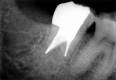

Successful endodontic treatment relies upon a thorough knowledge of root canal anatomical variations along with proper diagnosis, treatment planning, and clinical expertise. One of the difficult root canal configurations that are frequently encountered commonly in mandibular second molars is C-shaped root canal. Due to the intricate root canal configuration, it is often difficult to negotiate, debride, and obturate such canals leading to failure of root canal treatment. Understanding the anatomical variation and adequate visualization will enable the clinician to manage these cases effectively. Advanced irrigation and obturation techniques help in managing such anomalous canal configurations. This article presents the management of two different C-shaped root canal configurations under dental operating microscope using thermoplasticized obturation techniques.